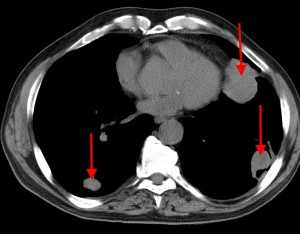

Перикард наиболее часто вовлечен в процесс метастазирования - на его долю приходится 64-69% всех сердечных метастазов. Метастазирование опухоли в перикард может привести к перикардиту с последующим развитием серозно-геморрагического или геморрагического выпота. Достоверную диагностику перикардиальной жидкости обеспечивают современная эхокардиография (Эхо-КГ) и компьютерная томография (КТ) сердца. На ранних этапах метастазирования клетки рака обнаружить трудно, на поздних стадиях онкологического заболевания опухолевые клетки также удается обнаружить далеко не у всех пациентов, однако установление злокачественной природы выпота до появления его клинических признаков имеет большое значение для правильного выбора тактики лечения. В случае тампонады сердца проводят «лечебный» перикардиоцентез, при острых перикардитах с массивным перикардиальным выпотом и выпотах неясной этиологии показано проводить диагностический перикардиоцентез. Для установления природы выпота необходимо цитологическое исследование эвакуированной жидкости. В большинстве случаев для постановки диагноза бывает достаточным цитологического исследования перикардиального выпота без исследования биоптата. В статье приведены два клинических случая метастазирования различных опухолей в перикард с развитием угрозы тампонады сердца.

Представлен клинический случай метастатической опухоли перикарда